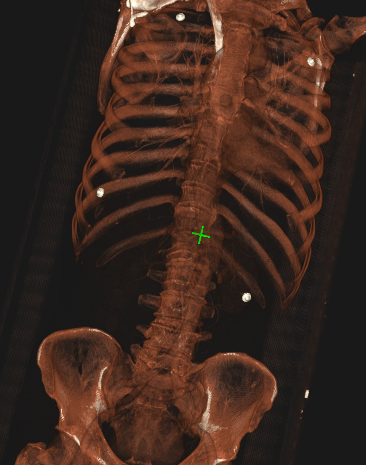

容积渲染 十字光标 被遮挡问题

VR模块的3DCursor功能,定位十字光标actor,头部被颅骨遮挡。

该怎么解? // 设置深度测试和渲染顺序 cursorMapper->SetResolveCoincidentTopologyToPolygonOffset(); cursorMapper->SetResolveCoincidentTopologyPolyg…